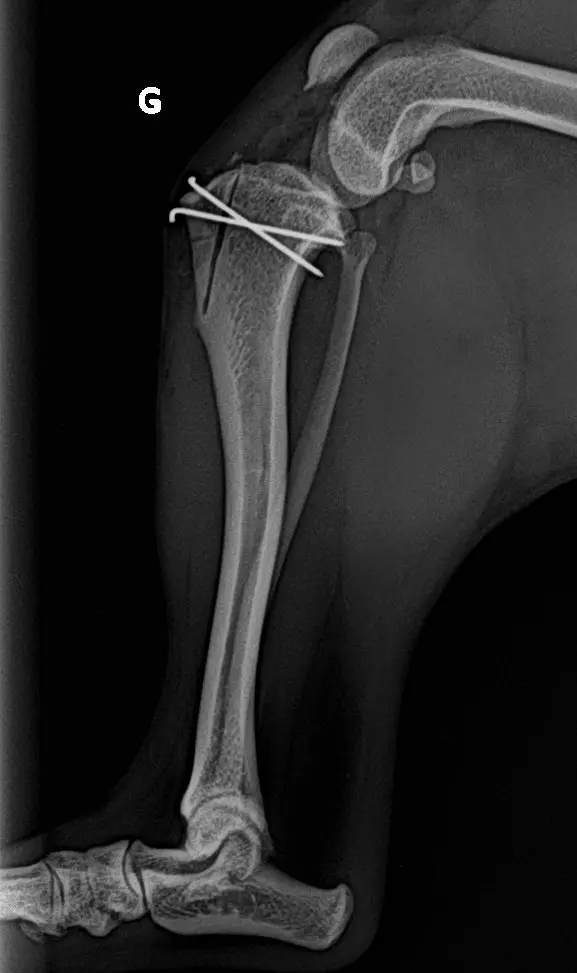

Luxation médiale de la rotule

- Repos strict pendant 4 semaines : garder votre animal en cage.

- Pas de saut ni de jeux, courtes sorties en laisse uniquement pour les besoins.

- Ne pas laisser votre animal lécher le pansement ou les sutures, maintenir la collerette jusqu’au retrait des points

- Les pansements peuvent se décoller et tomber dans les prochains jours, ils ne doivent pas être renouvelés.

- Retrait des points dans 12-14 jours chez votre vétérinaire traitant.

- Contrôle radiographique dans 4 semaines